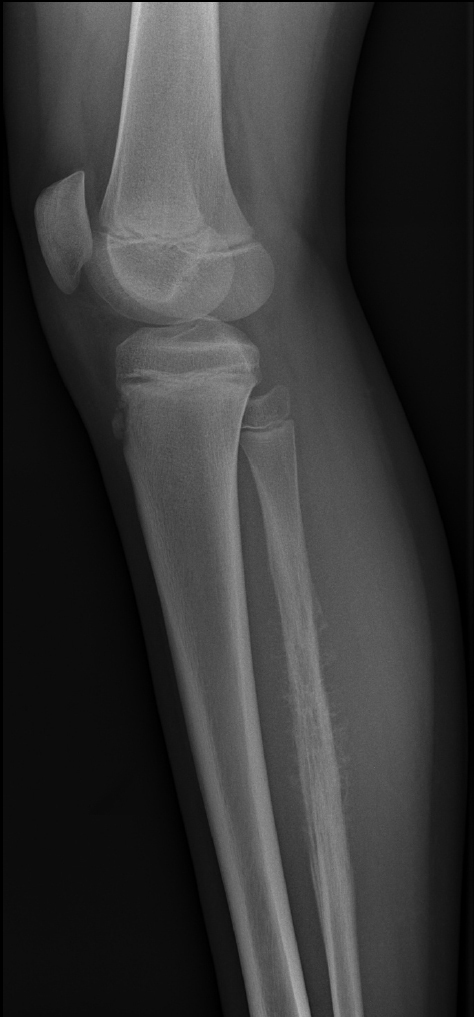

Auch wenn sich Osteosarkom und Ewing-Sarkom bildgebend nicht sicher voneinander unterscheiden lassen, zeigen beide Entitäten charakteristische Häufungen bestimmter morphologischer Merkmale. Auf den beiden vorliegenden Röntgenaufnahmen sehen Sie jeweils eine Knochenläsion – einmal der Tibia und einmal der Fibula. Welche Läsion ist eher einem Osteosarkom, welche eher einem Ewing-Sarkom zuzuordnen, und welche radiologischen Merkmale stützen diese Einschätzung?